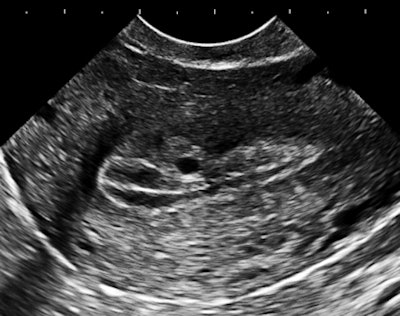

The importance of image contrast is demonstrated in these endovaginal images of a 36-year-old nulliparous woman with heavy and irregular periods due to adenomyosis.

| Above and below: Endovaginal images of a 36-year-old nulliparous woman with heavy and irregular periods due to adenomyosis. |

Adenomyosis (i.e., gland tissue in muscle) occurs when the integrity of the endometrial boundary is disrupted and rapidly growing, vigorous endometrial cells migrate from the city to the myometrial suburbs. Glandular tissue is highly vascularized, leading to the typical 2D Doppler findings with the clinical presentation of heavy, often painful menstruation with clots. There may be small secretory cysts.

The border zone irregularities reconcile the ultrasound findings with pathology and with the classic sign of hysterosalpingography for this condition. This is a grayscale contrast issue. Over the years, I have come to regard contrast as the most important determinant of image quality for all applications of ultrasound.